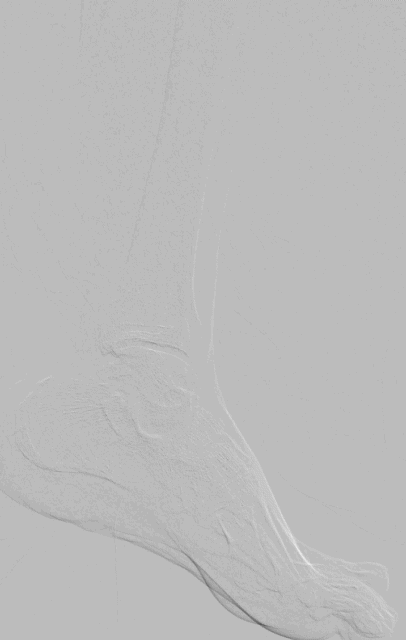

手术过程(四):踝下血管经足底动脉弓腔内成形(PPL)开通

图片

2、膝下动脉胫前胫后全程闭塞,钙化严重,长度均超过30cm,同时踝下流出道不佳,应用PPL技术开通足弓动脉,保证流入道及流出道通畅,远期通畅率会更高。